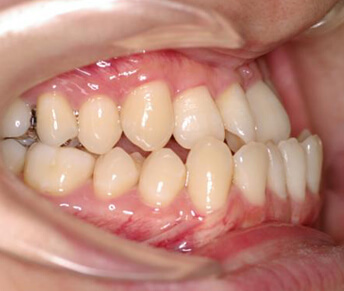

歯列矯正治療には幾種かの装置があります。

装置別のメリット、デメリットを認識し治療に望むことは治療の第一歩であり、それは治療の成果に大きく影響します。

- メタルブラケット装置

メリット

- ・装置自体が金属性で強度が高いので小さく出来ている為、違和感が少なく口内炎もできにくい。

- ・強度が高いので壊れたり、外れたりし難いので治療期間が長引く可能性が少ない。

- ・装置とワイヤーが金属同士なので滑りが良く歯が動きやすいので治療期間が短く出来る。

- ・強度が高いので強い力をかけても壊れにくい為強い力で正確に歯をコントロールでき、より良い治療結果を得る事ができる。

デメリット

- ・装置が目立つ